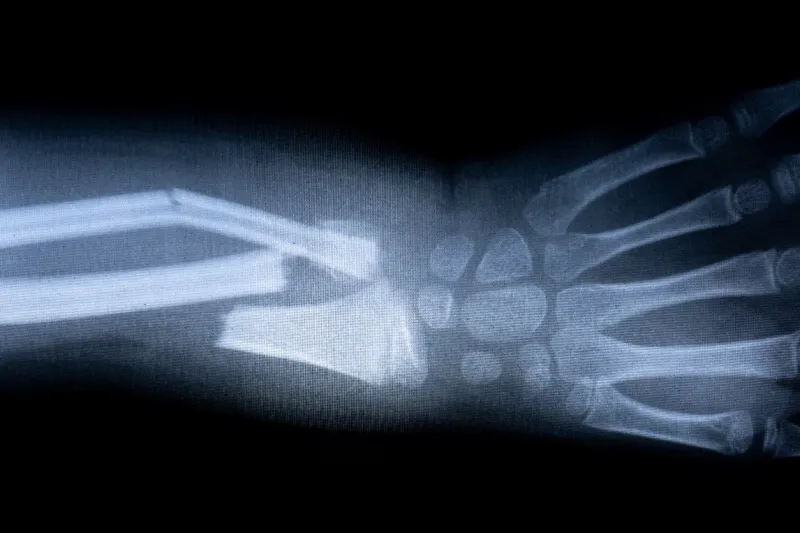

Les os cassés

x-ray film skeleton human arm health medical anatomy body concept

Briser un os peut être incroyablement douloureux. Les fractures de la cheville, de la hanche, du bras et du nez sont parmi les blessures les plus douloureuses, estime le NHS.